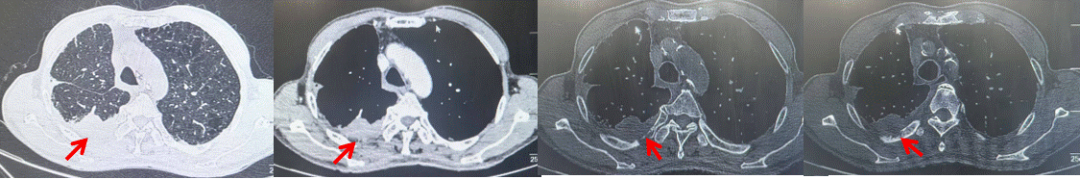

69岁男性,无糖尿病、高血压、心脏病等基础疾病,无吸烟、饮酒史,无肿瘤家族史。2023.06.07行胸部CT检查:右肺上叶胸膜下见肿物影,大小约33mm×22mm,边缘可见分叶,考虑恶性病变可能性大,双肺间质改变(如图1)。2023.06.14行“单孔胸腔镜下右肺上叶切除、肺门及纵隔淋巴结清扫、胸膜粘连松解术”;术后病理:(右肺上叶)腺癌(低分化,实体型占60%,不良腺体占40%),局灶伴神经内分泌标记表达(CD56、Syn),可见STAS及胸膜侵犯,未见确切神经侵犯及脉管内癌栓;(气管切缘)净;(淋巴结)未见转移癌0/26(2组0/2;4组0/6;7组0/2;对侧7组0/8;10组0/2;11组0/3;12组0/2;13组0/1)。术后分期pT2aN0M0 IB期,术后NGS基因检测:无驱动基因突变,PD-L1(22C3)TPS<1%。术后定期复查。

图1:患者手术前(2023.06)胸部CT肺窗及纵隔窗